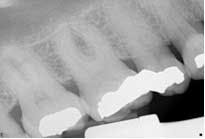

Figs. 4 and 5: Radiographs of tooth No. 3: Five-canal molar with two mesial and two distal canals present

The obturation technique included warm vertical condensation with continuous wave and AH-plus sealer and backfilled all the canals to their respective orifice. Cotton and cavit g temporary restoration were again placed more than 3 mm from the occlusal surface to prevent coronal micro-leakage in the access cavity. The occlusion checked, postoperative instructions were written and verbally given. Two periapical radiographs were exposed to illustrate the unique anatomy. (Figs. 4 and 5)